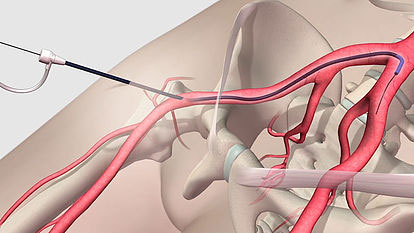

Angioplasty & Stent Placement

Angioplasty is a minimally invasive procedure used to open narrowed or blocked arteries. A thin catheter with a small balloon...